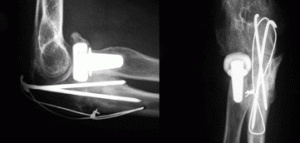

CASO CLÍNICO ARTICULACIÓN DEL CODO. PRÓTESIS DE CABEZA DE RADIO (PARTE I)

Mujer de 45 años de edad que sufre una caída montando en bicicleta el 27 de agosto de 2013, produciéndose una luxación posterior de codo con fractura de la cabeza del radio. El 30 de agosto de 2013 se [...]

CASO CLÍNICO ARTICULACIÓN DEL CODO. PRÓTESIS DE CABEZA DE RADIO (PARTE II)

Continuamos con el caso clínico de prótesis de cabeza de radio que publicamos previamente en nuestro apartado de casos clínicos.